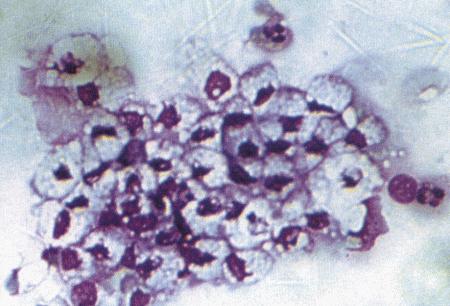

Фиг. 1.3.

Эндоскопическое исследование слизистой влагалища. Динамика изменений на протяжении цикла: (а) проэтрус — розовая окраска и отечность; (b) начало эструса — слизистая бледнеет, отек начинает уменьшаться (обычно перед пиком ЛГ); (c) середина эструса — слизистая бледная, уменьшение отека (сморщивание) явно выражено, что соответствует середине фертильного периода; (d) начало метэструса — видны закругленные складки, при прикосновении слизистая смыкается, образуя розетку (е) (см. Приложение)